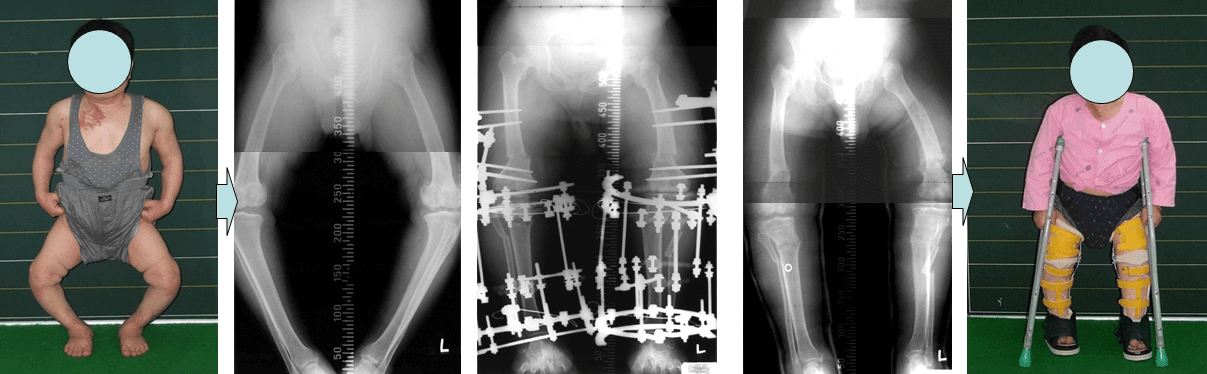

A patient with pseudoachondroplasia whose legs were twisted received correction with the Ilizarov method.

Perform ilizarov technique to treat twisted legs caused by pseudoachondroplasia.